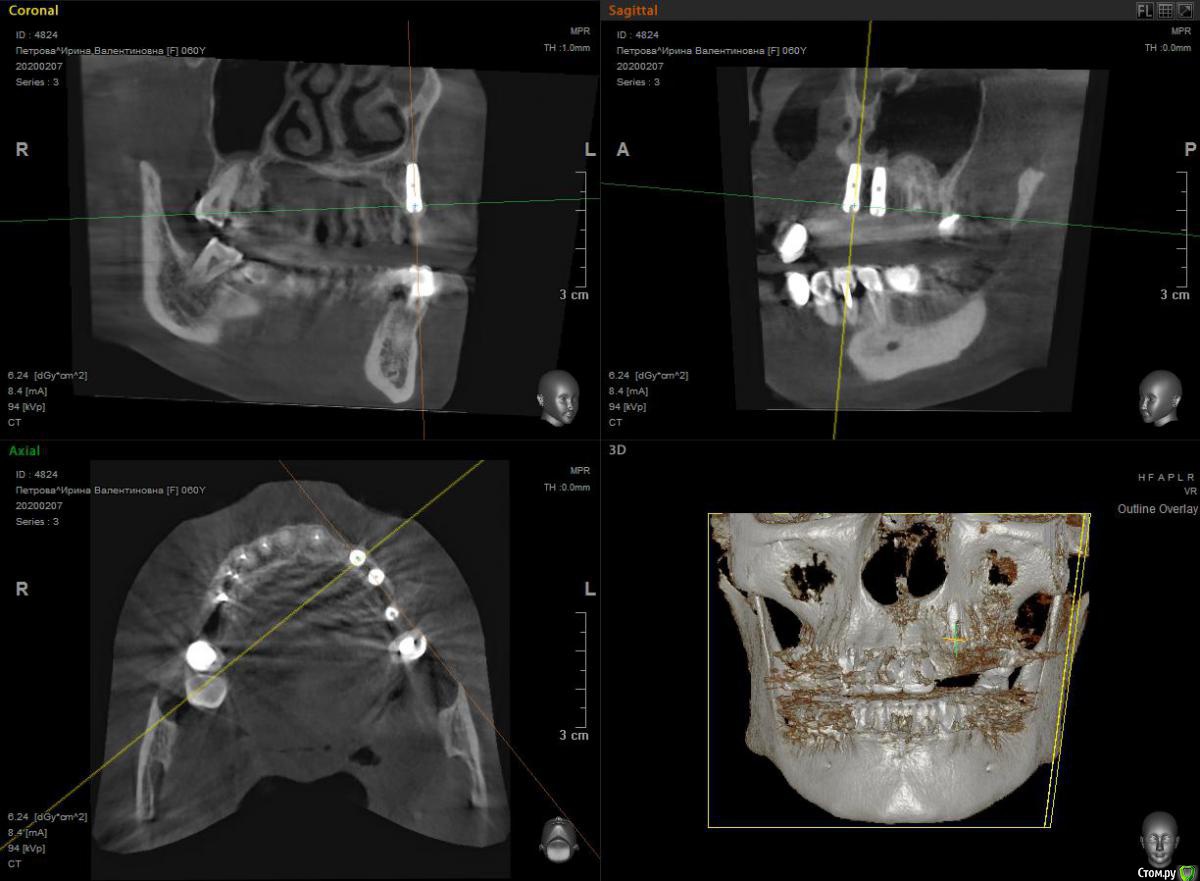

HAV Опубликовано 7 февраля, 2020 Поделиться Опубликовано 7 февраля, 2020 Здравствуйте. Посоветуйте пожалуйста, как поступить - выкрутить и переустановить имплантат, или выполнить НКР вестибулярно? Операция выполнена два месяца назад. Ссылка на комментарий

HAV Опубликовано 7 февраля, 2020 Автор Поделиться Опубликовано 7 февраля, 2020 То есть, считаете - вообще туда лезть не стоит? Если тонкий битип - подшить ССТ на втором этапе!? Ссылка на комментарий